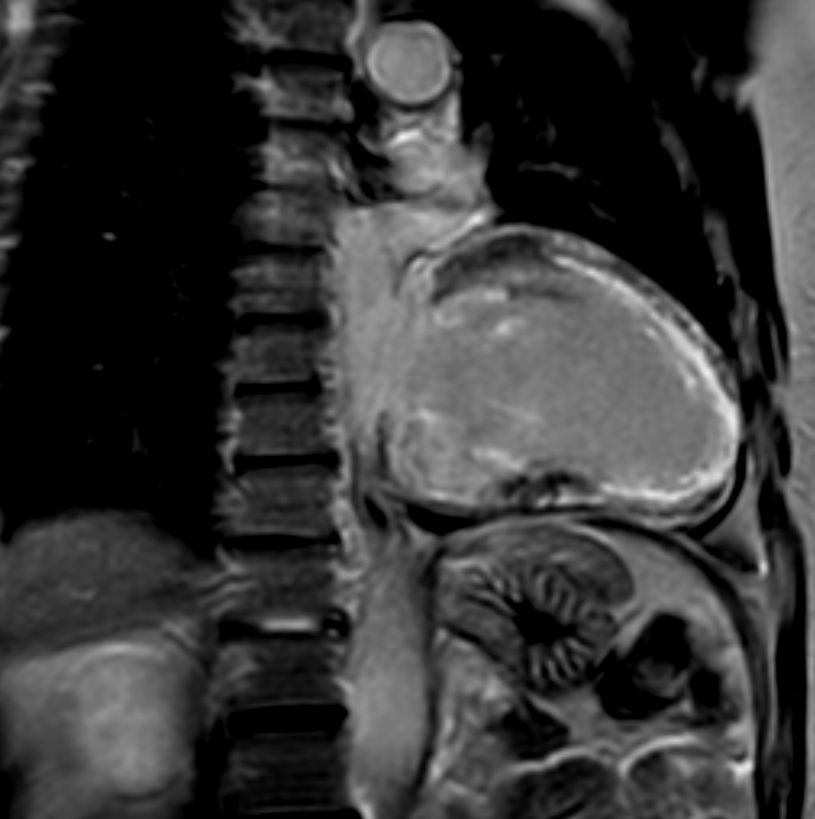

2 chamber view cine

2 chamber view T2w Black Blood